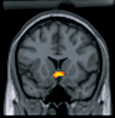

FMRI BrainNew research reveals why a stimulus that healthy human subjects perceive as a reward might be processed quite differently in the brains of humans suffering from chronic pain. The study, published by Cell Press in the April 15 issue of the journal Neuron, provides fascinating insight into an apparent switch in neural circuitry that may be an integral part of the pathophysiology of chronic pain.

Dr. Apkarian and colleagues used functional magnetic resonance imaging (fMRI) to compare brain activity in response to acute noxious thermal stimuli in healthy control subjects and in patients with chronic back pain. The researchers found that pain perception and related brain activation patterns were nearly identical in the two groups. However, there was one profound difference in the activity of a specific part of the brain called the nucleus accumbens.

The nucleus accumbens has been extensively researched with regards to its role in reward and motivation, but how it fits into circuitry underlying the response to aversive events or chronic pain is not clear. In the current study, the researchers discovered that phasic nucleus accumbens activity at the beginning of painful stimuli predicted pain perception and at termination of painful stimuli predicted reward (pain relief) in the healthy group. In the subjects with chronic back pain, nucleus accumbens activity correlated with different neuronal circuitry than the controls, and its phasic activity at the end of the stimulus was in the opposite polarity than the healthy subjects, suggesting that the acute pain relieved the ongoing back pain.